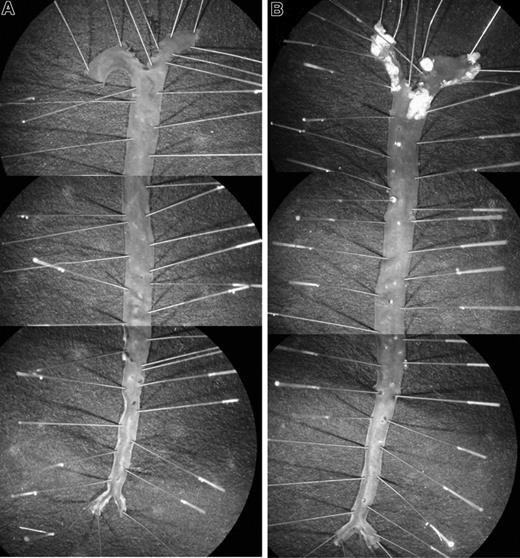

Littermates of various genotypes (apoE+/+HCII+/+, apoE−/−HCII+/+, apoE+/+HCII−/−, and apoE−/−HCII−/−) were fed a Western diet between the ages of 8 and 20 weeks and were then killed. Figure 1 shows typical images of pinned aortas obtained from apoE+/+HCII−/− and apoE−/−HCII−/− mice. Atherosclerotic lesions in apoE−/− mice were clearly demarcated from the surrounding normal intimal surface. No lesions were observed in apoE+/+ mice regardless of the HCII genotype. In the apoE-null background, however, atherosclerotic plaque areas were significantly greater in HCII−/− mice in comparison with HCII+/+ mice in the aortic arch (18.0% ± 4.7% vs 11.1% ± 3.0%, P = .001) but not in the thoracic aorta (4.4% ± 2.2% vs 2.8% ± 2.3%, P = .117) (Figure 2). Although the lesions in apoE−/−HCII+/+ and apoE−/−HCII−/− mice differed in total area, they were similar in gross appearance. No lesions were present in the abdominal aorta. Serum cholesterol, triglycerides, free fatty acids, and glucose were elevated in apoE-null mice as previously reported,21 but these parameters were unaffected by the HCII genotype (Table 2). In apoE+/+ mice, the HCII genotype did not affect the cholesterol, triglyceride, or glucose concentrations, but HCII−/− mice had approximately 30% lower levels of free fatty acids (P = .04).

Atherosclerotic lesions. Typical appearance of aortas from apoE+/+HCII−/− (A) and apoE−/−HCII−/− (B) mice. Mice were fed a Western diet beginning at 8 weeks of age and were killed at 20 weeks of age. To show the entire aorta in a single image, each panel is a composite of 3 adjacent microscopic fields. Atherosclerotic plaques are present in the aortic arch and to a lesser extent in the thoracic aorta of the apoE−/−HCII−/− mouse (B).

Experiments in which injured arterial segments from HCII−/− mice were incubated with tosyl-Gly-Pro-Arg-p-nitroanilide for 2 hours, then rinsed with buffer and incubated with fresh substrate, revealed that the rate of substrate hydrolysis was unchanged after rinsing (data not shown). This observation suggested that the thrombin remained active and stably associated with the vessel. To determine the location of thrombin activity in the vessel wall, we prepared frozen sections of carotid arteries harvested 1 hour after injury, incubated them with hirudin, and then detected the bound hirudin with an antibody. Hirudin binding was observed only in the injured vessels from HCII−/− mice (Figure 6), where it was located predominantly in the intima and media. Staining was less intense in the adventitia and in thrombi present in the lumen of the vessel.

Binding of hirudin to arterial sections. Frozen sections were prepared from carotid arteries of HCII−/− (A,C) or HCII+/+ (B,D) mice harvested 1 hour after injury. The sections were then incubated with hirudin in vitro, and bound hirudin was detected with sheep anti–hirudin IgG and a secondary antibody linked to peroxidase (C,D). Controls in which the primary antibody was omitted are shown (A,B). A thrombus is visible in the arterial lumen of the HCII−/− mouse. IEL indicates internal elastic lamina; EEL, external elastic lamina.